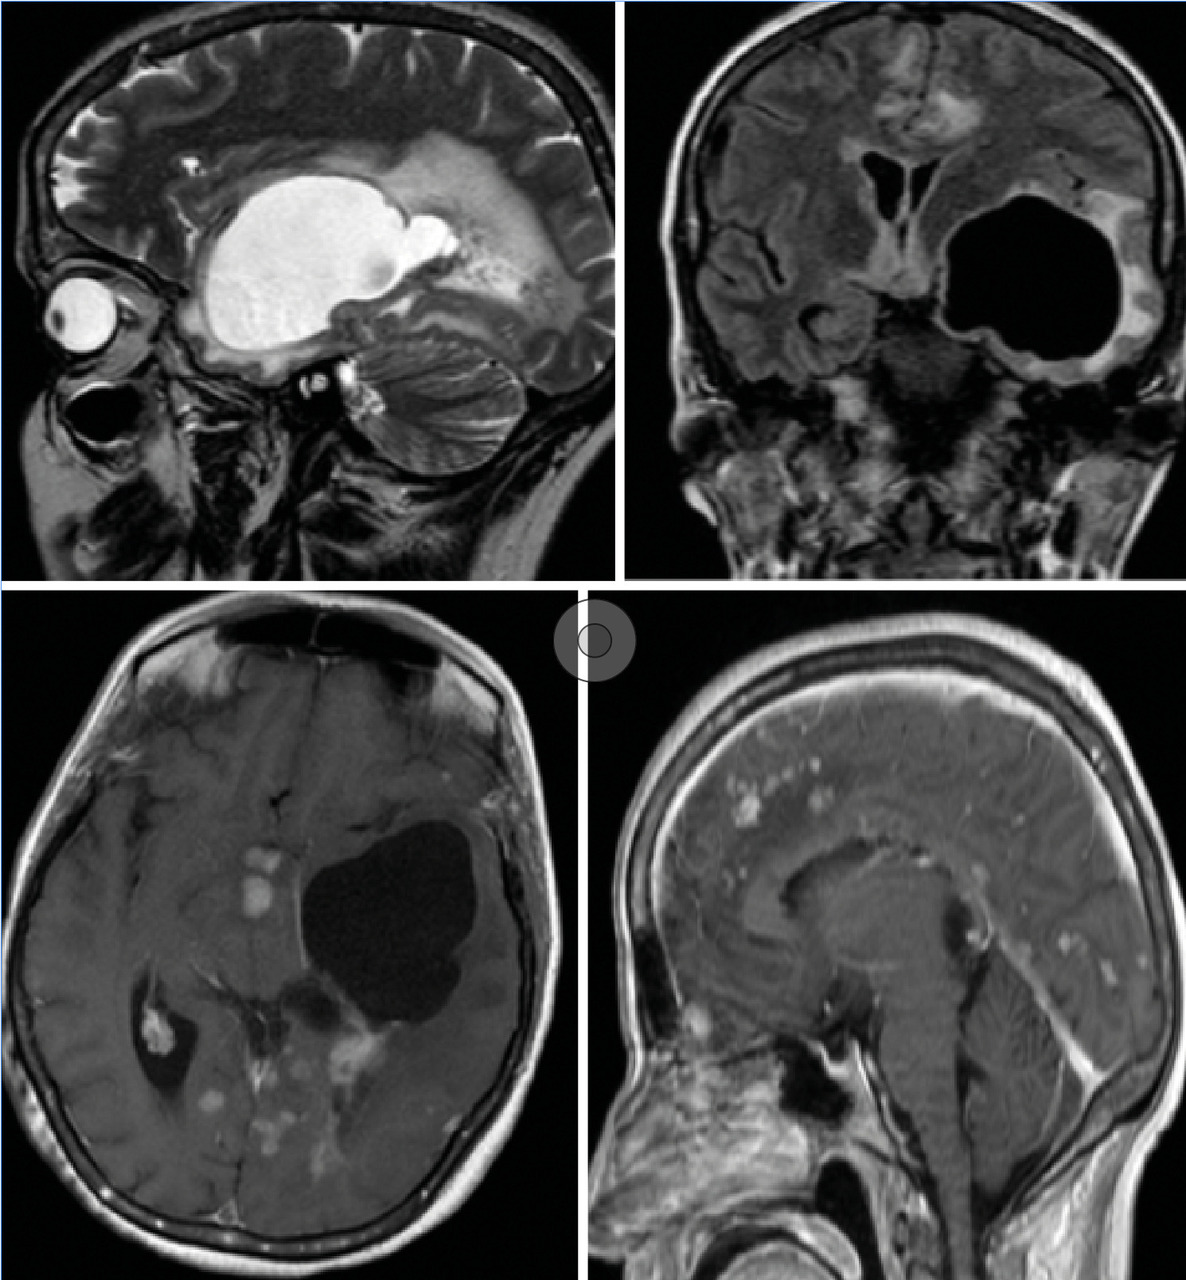

Cette femme de 44 ans avait un tableau d’hypertension intracrânienne et des troubles du comportement, un syndrome pyramidal droit, une paralysie faciale centrale droite, un syndrome confusionnel et un œdème papillaire ; pas de particularité pour le reste de l’examen, notamment pulmonaire. Le bilan biologique (test de sensibilité à la tuberculine, antigène carcinoembyonnaire, métabolisme calcique, cytologie du lavage bronchoalvéolaire) et la radiographie pulmonaire étaient normaux. La tomodensitométrie (TDM) cérébrale (fig. 1 ) montrait une lésion kystique temporale gauche exerçant un effet de masse sur la ligne médiane avec un œdème périlésionnel. Après injection il y avait une prise de contraste micronodulaire leptomeningée diffuse et de la corne occipitale du ventricule latéral gauche. L’imagerie par résonance magnétique (IRM) [fig. 2 ] montrait une volumineuse lésion kystique expansive temporale gauche, dont les parois ne se rehaussaient pas après injection du produit de contraste avec un hypersignal T2 périlésionnel ainsi qu’un engagement temporal. La résection chrirugicale et la corticothérapie permettaient une amélioration neurologique immédiate. L’histologie était en faveur d’un granulome épithéloide gigantocellulaire sans nécrose caséeuse.

La sarcoïdose est une granulomatose systémique de cause inconnue, elle peut atteindre l’ensemble du système nerveux : nerfs crâniens, parenchyme cérébral, leptoméninges et nerfs périphériques. L’atteinte neurologique peut être inaugurale et le diagnostic est alors difficile.1 Six à 30 % des patients ayant une neurosarcoïdose ont une hydrocéphalie soit communicante par altération de la résorption du liquide céphalorachidien (LCR), soit plus fréquemment obstructive du fait d’une infiltration granulomateuse de l’épendyme et des plexus choroïdes. Une forme rare d’hydrocéphalie obstructive est représentée par les trapped ventricular compartements, qui peuvent concerner le 4e ventricule, la corne temporale des ventricules latéraux, prenant le nom d’entrapped temporal horn, elle est la conséquence d’un obstacle à la circulation du LCR au niveau du trigone du ventricule latéral, résultant de l’infiltration granulomateuse de l’épendyme et du plexus choroïde, isolant la corne temporale contenant le plexus choroïde du reste du système ventriculaire. Du fait de la présence du plexus sécrétant du LCR, la cavité s’agrandit progressivement et se comporte comme un processus expansif.